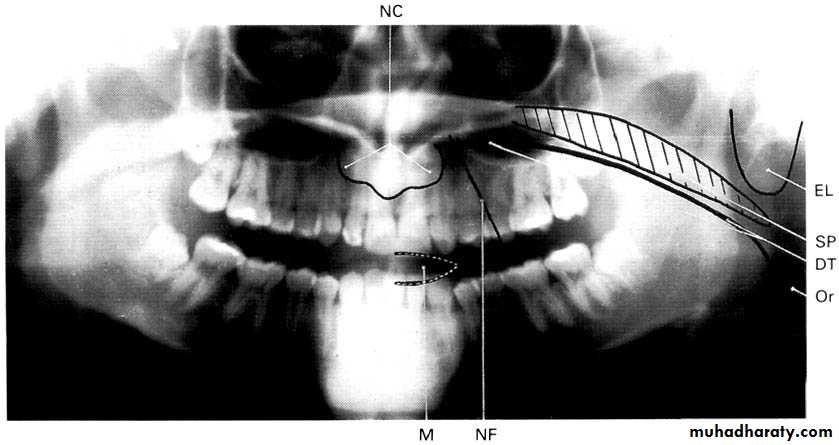

A dental panoramic tomograph showing the main real soft tissue and air shadows drawn in on

one side of the radiograph, NC — nasal cartilages, EL — ear lobe, SP — soft palate,DT — dorsum of tongue, Or — oropharnyx, NF — naso-labial fold, M — mouth.